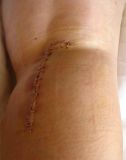

1. Popliteal extraskeletal chondroma of the right knee in a 38-year-old female.

Treatment: Surgical removal

I. Before the surgery , lateral x-ray of the knee shows the chondroma (red arrow) II. Post-surgery, lateral x-ray of the knee shows that the chondroma has been removed III. Post-surgery, the photo (posterior site of the knee) is showing the specific approach that has been used for the operation.